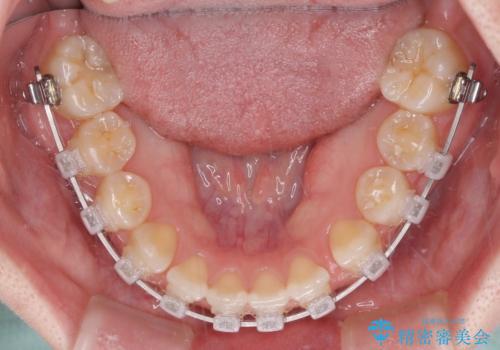

- クリアブラケット

口腔内の状況を確認したところ、左右ともに下顎第二大臼歯が欠損しており、咬み合うべき上顎の第二大臼歯が著しく挺出していました。

挺出した大臼歯を元の位置に戻すことは現実的に難しいため抜歯することとし、補助装置とワイヤー装置により上顎歯列全体を後方に移動することとしました。

順調に後方移動することができ、わずか1年強で治療を終えることができました。